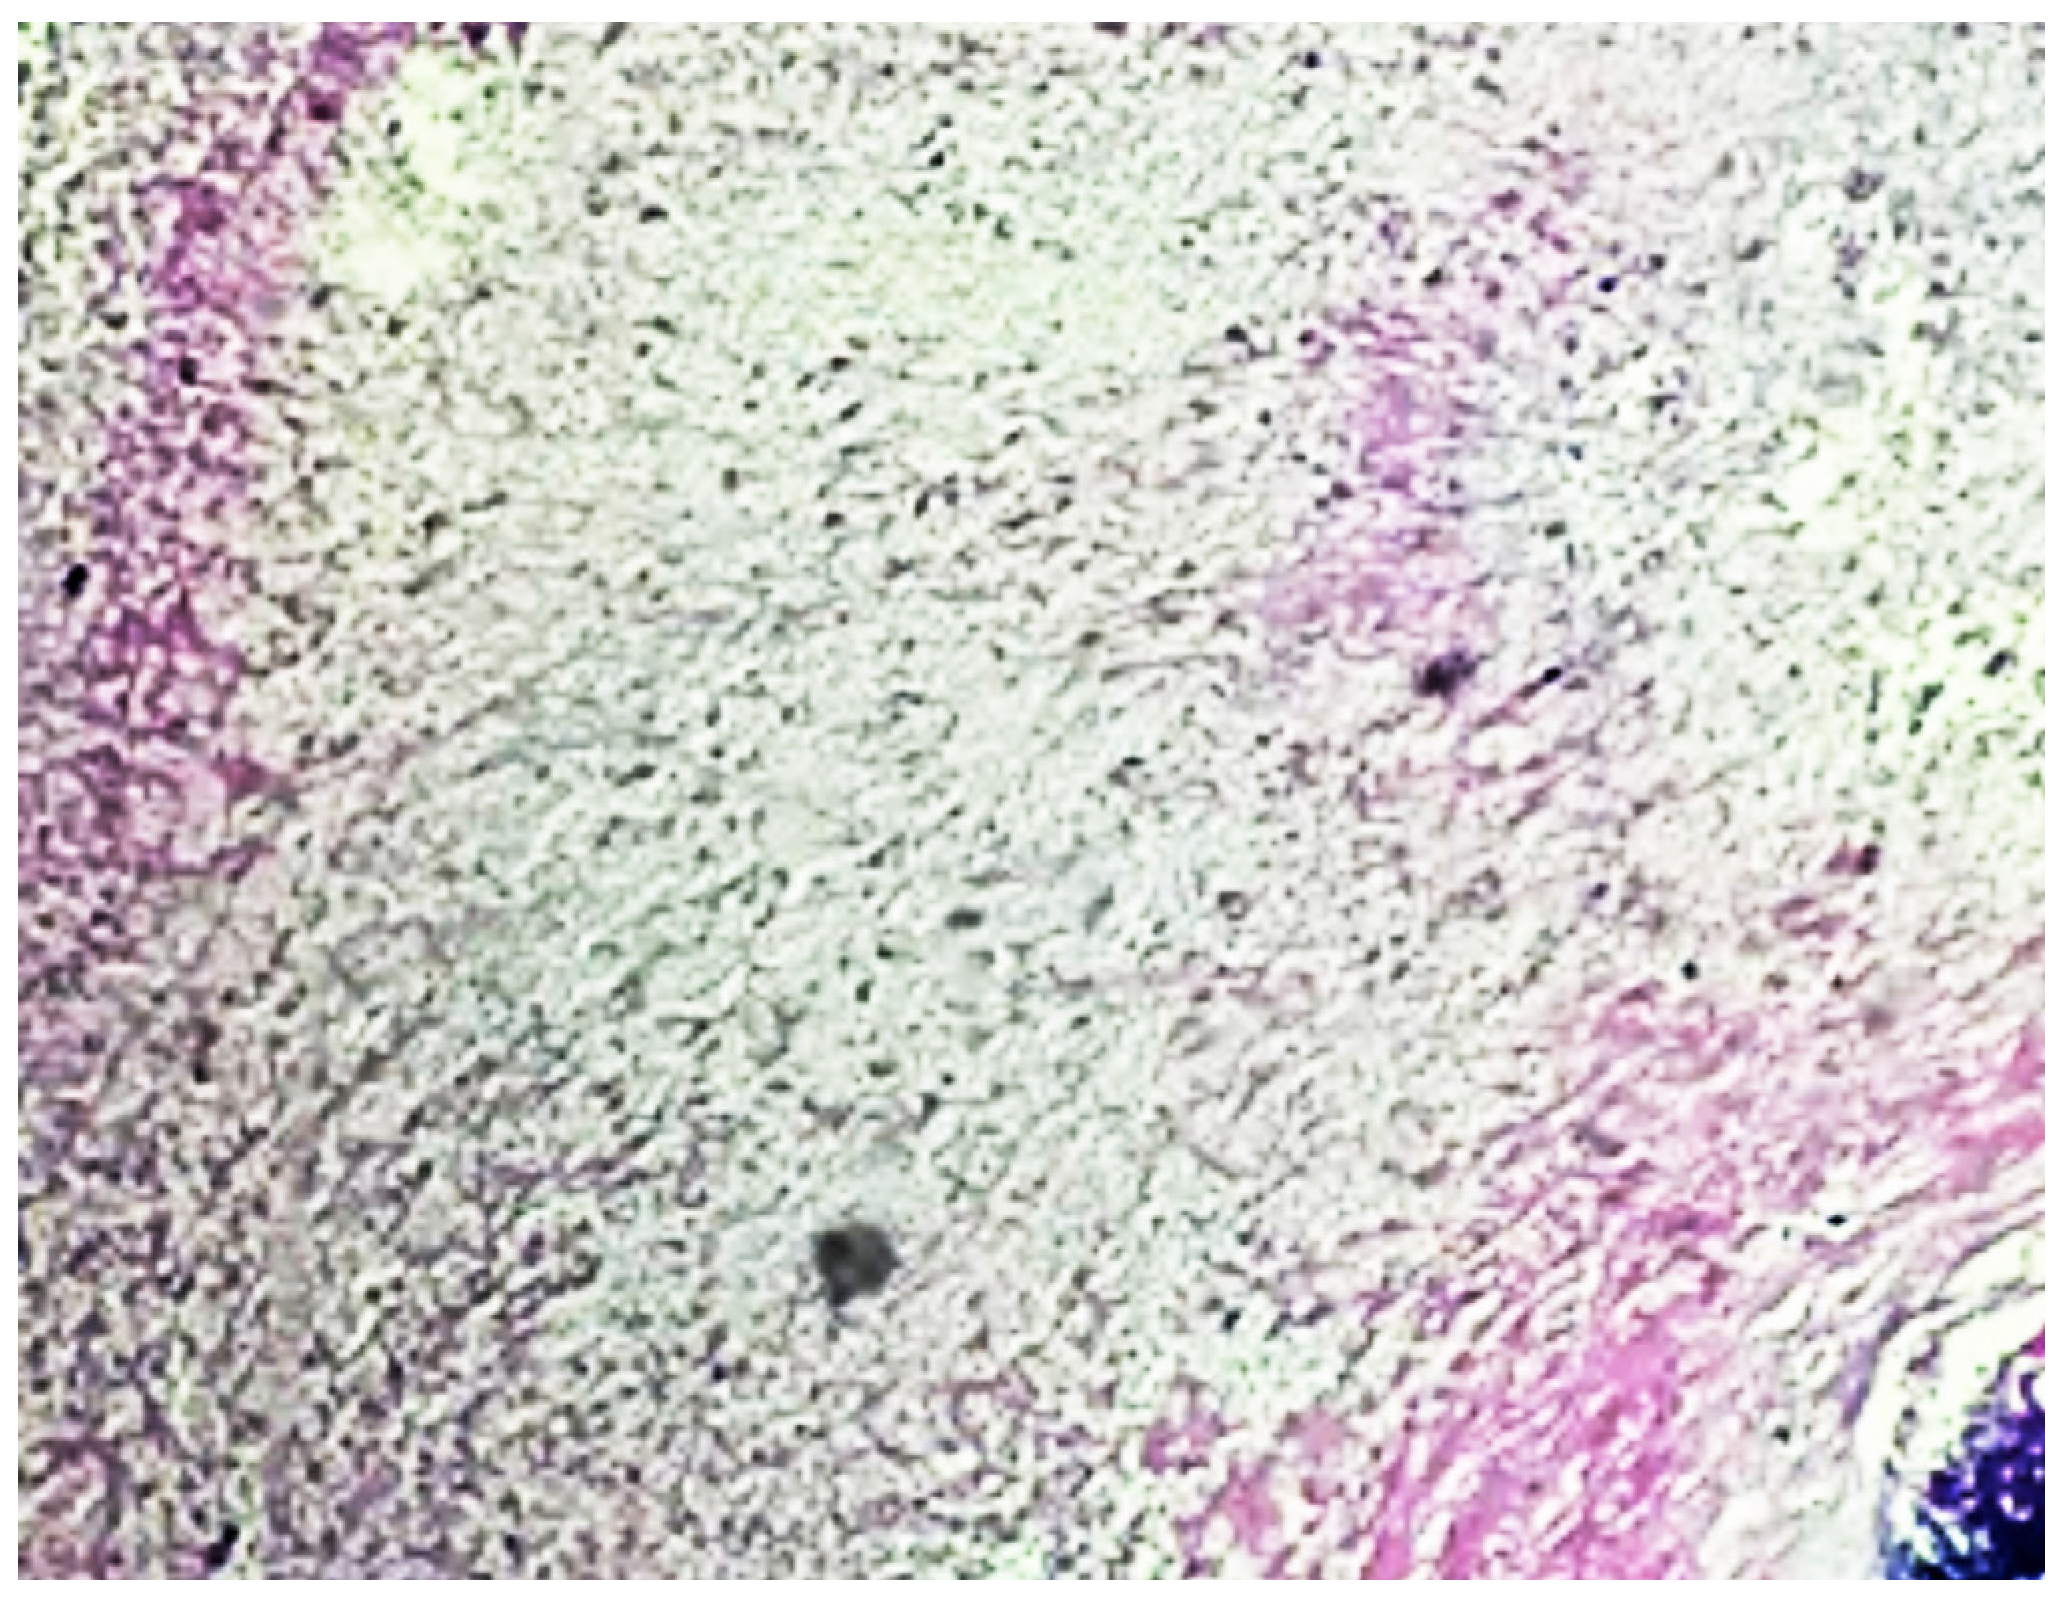

Burned-Out Bladder Tumor